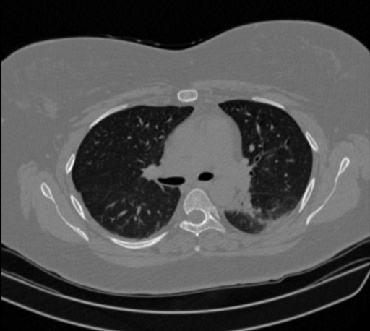

Figure 1 shows four CT scan slices, two from a non-COVID-19 CT scan, on the left and two from a COVID-19 scan, on the right. Bilateral ground glass regions are seen especially in lower lung lobes in the COVID-19 slices.